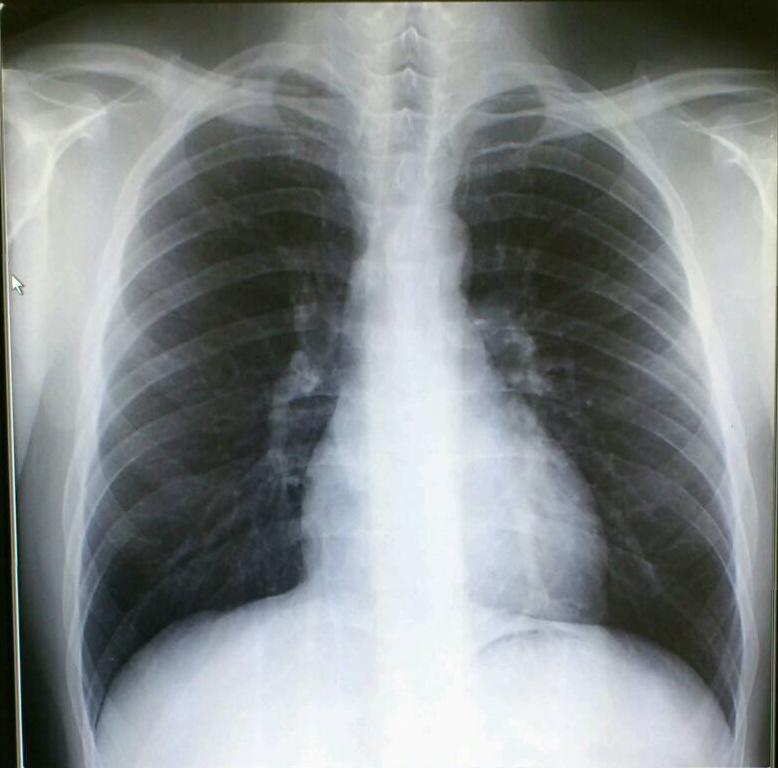

レントゲン検査

胸部レントゲン検査では、肺炎・肺がん・結核・COPDなどの診断ができます。